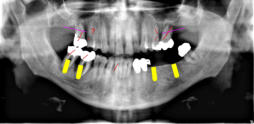

Beispiele für komplexe implantologische Versorgungen aus unserer Gemeinschaftspraxis

(Planung / Endversorgung -- als Röntgenaufnahmen)

C3